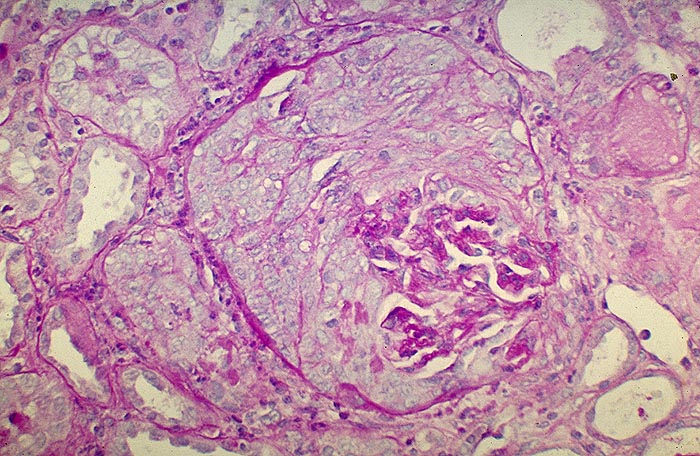

Extrakapillär betonte Glomerulonephritis: globaler Halbmond

Der Kapselraum des Glomerulus wird durch proliferierte Zellen eines globalen Halbmondes, der das gesamte Schlingenkonvolut umgibt, vollständig ausgefüllt. Die Glomerulusschlingen sind im Bereich des Gefässpols zusammengesintert. Keine Zellvermehrung im Schlingenkonvolut.

Beim Goodpasture Syndrom kommen nicht nur in den Nieren, sondern auch entlang der alveolären Basalmembran ultralineare Ablagerungen von Antibasalmembran Antikörpern vor. Gehäuft bei Rauchern, nach Virusinfekten, nach Rifampicin oder bei malignen Tumoren.